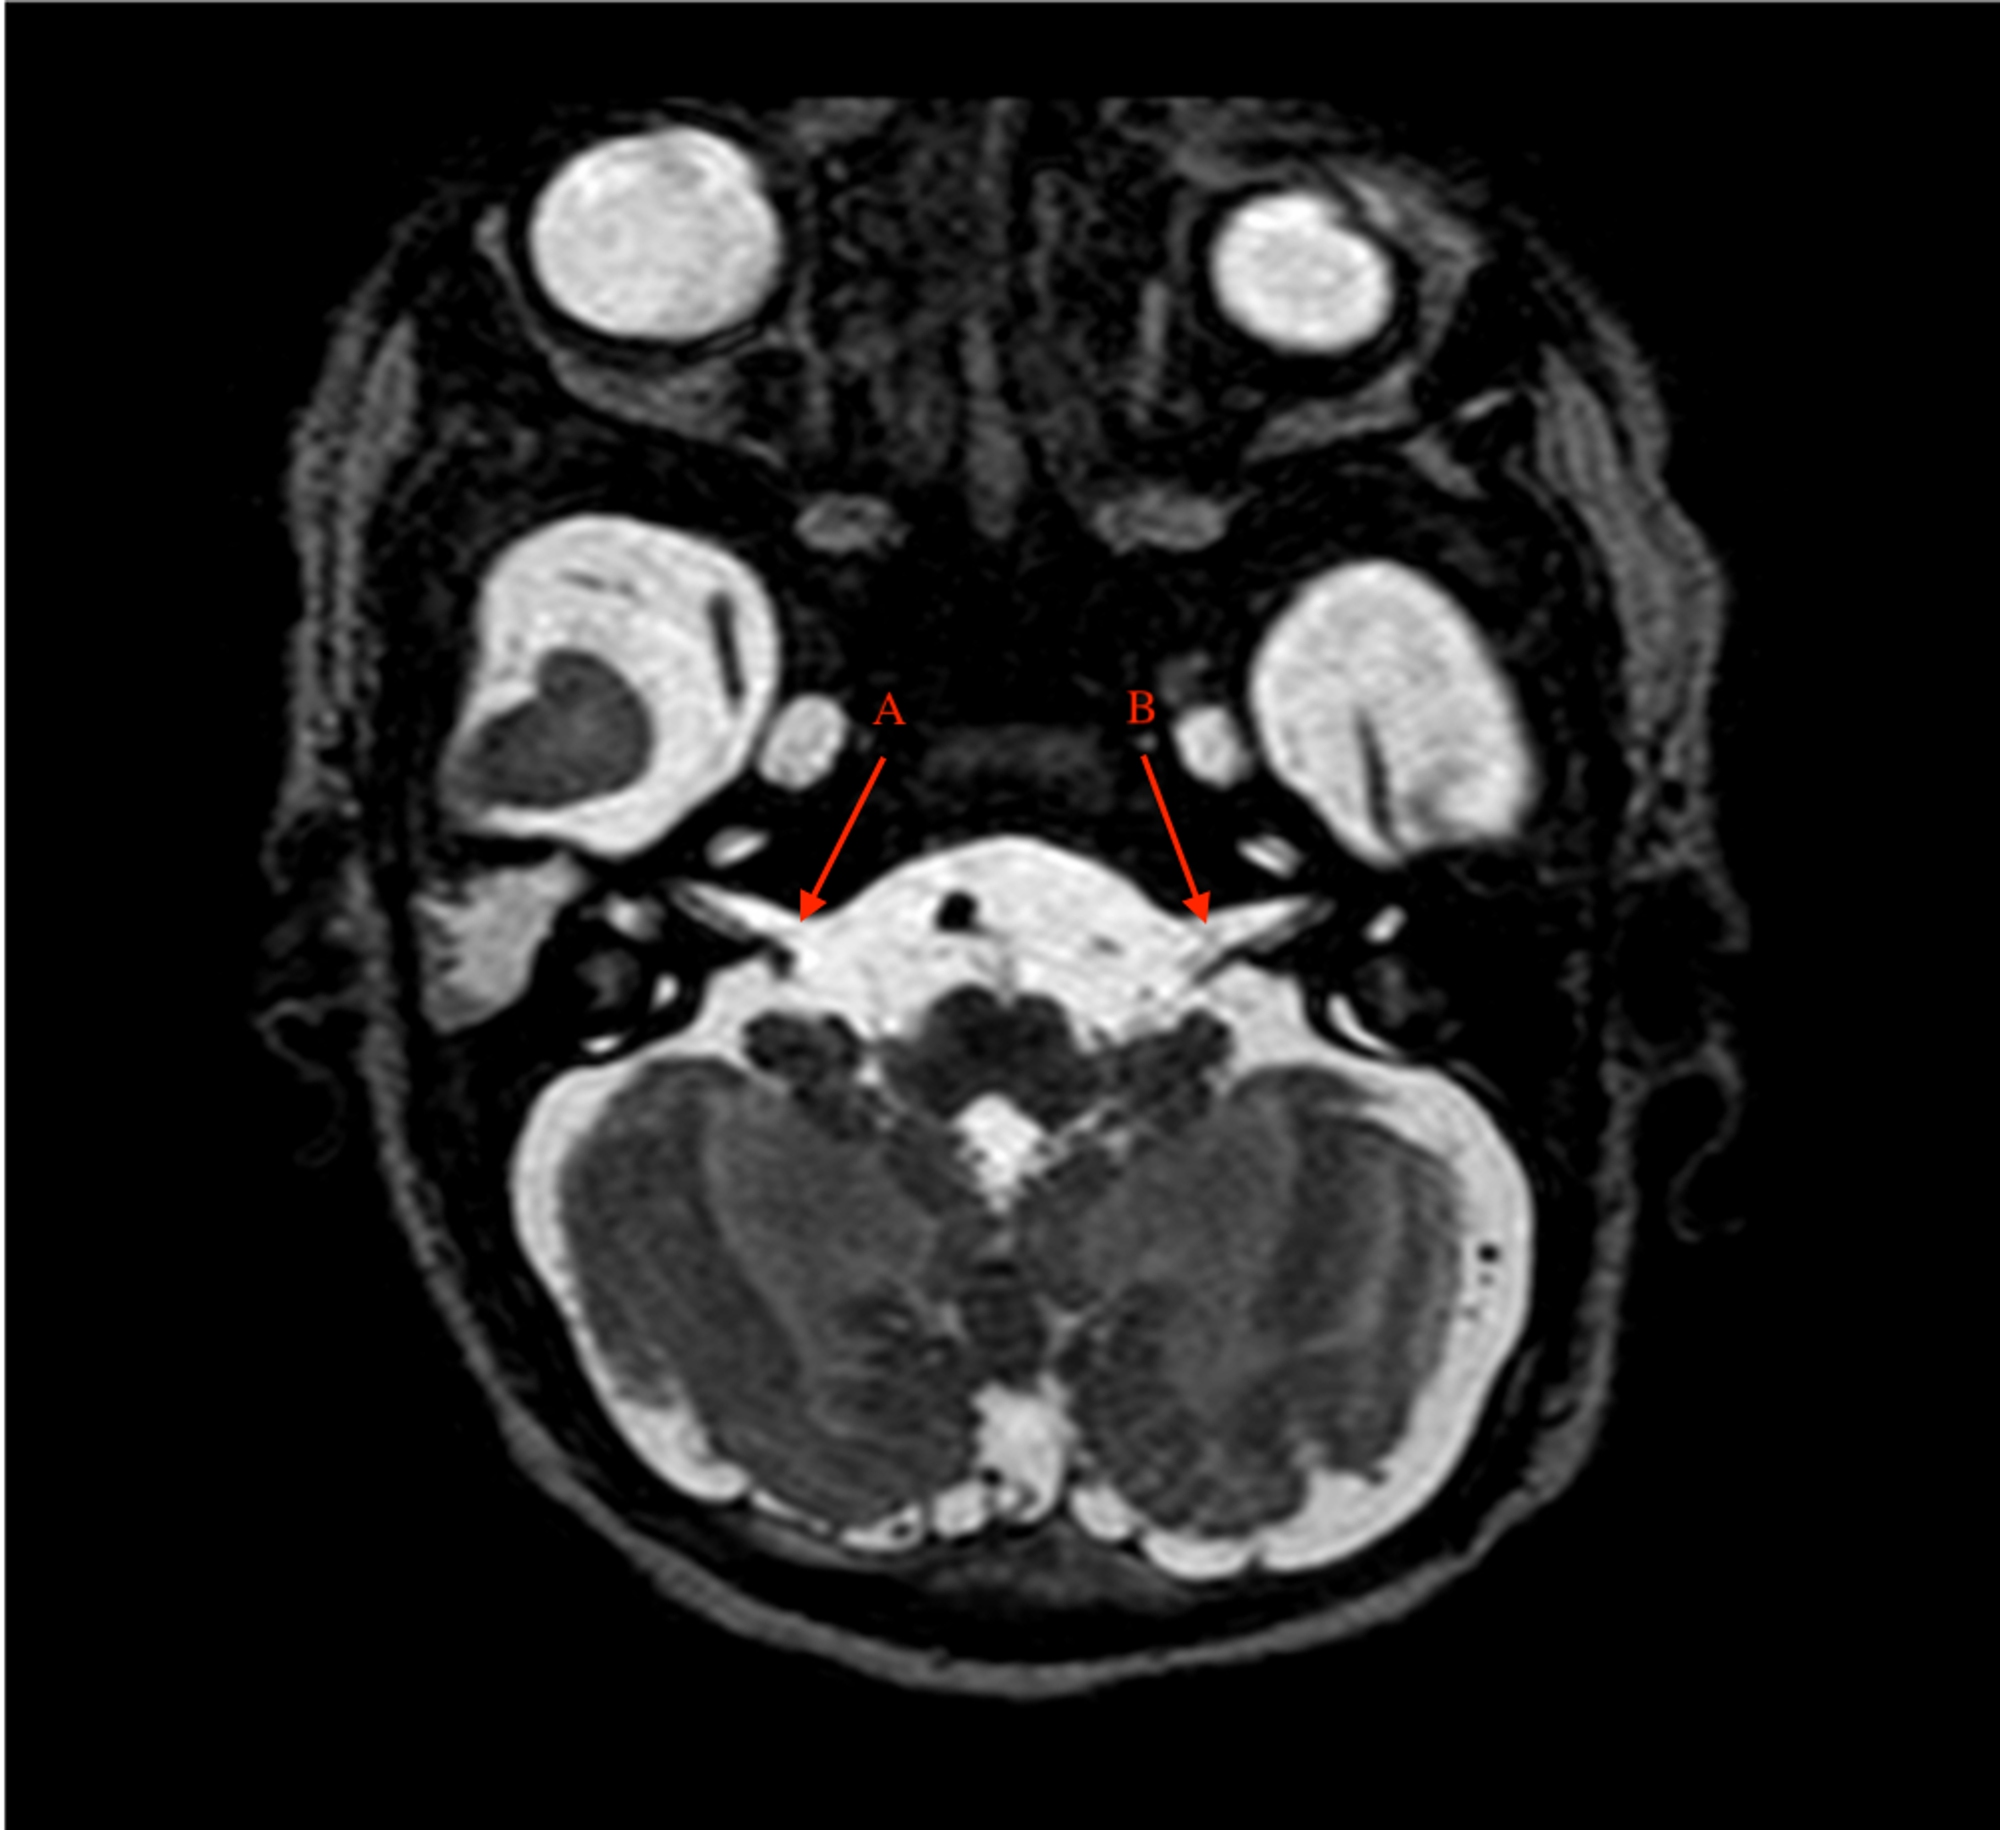

Dr Bahman Rasuli ◉ and Assoc Prof Frank Gaillard ◉ ◈ et al . Facial colliculus syndrome refers to a constellation of neurological signs due to a lesion at the facial colliculus, involving: abducens nerve (CN VI) nucleus facial nerve (CN VII) fibers at the genu

Facial Colliculus Syndrome Contributor: Christopher Kirkpatrick, MD The facial colliculus is an anatomic elevation on the floor of the 4th ventricle located medial to the sulcus limitance in the dorsal pons .

Facial colliculus pathology causes LMN type of facial palsy, diplopia and horizontal conjugate gaze palsy . The abducens nerve innervates the ipsilateral lateral rectus muscle and directly controls abduction in the ipsilateral eye .

The facial colliculus is an elevation on the floor of the fourth ventricle in the pons under which is located the abducens nucleus (cranial nerve VI) and the axons of the facial nerve nucleus (VII), which arc around the abducens nucleus . From: Netter's Atlas of Neuroscience (Third Edition), 2016

This rare condition, particularly when isolated, is caused by circumscribed lesions of the pontine tegmentum involving the abducens nucleus, the ipsilateral medial longitudinal fasciculus, and the adjacent facial colliculus . Its recognition is therefore of considerable diagnostic value .

When this lesion also affects the fascicle of the the ipsilateral facial nerve (CN VII) in the region of the facial colliculus as it wraps around the CN VI nucleus, it produces a lower motor neuron pattern of ipsilateral facial weakness . When this occurs, a one-and-a-half syndrome plus a 7th nerve palsy, it is termed an eight-and-a-half syndrome .